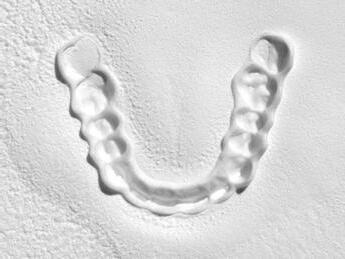

Finalmente, las restauraciones se cementaron adhesivamente (Figuras 31-35). En las piezas 16 y 17 se realizaron restauraciones cementoatornilladas como última fase de tratamiento. Se recomendó al paciente una férula de protección superior la cual fue elaborada mediante un flujo de trabajo digital (Figura 36)

Figura 36. Férula de protección.

Férula de Descarga Digital de Nylon

La primera Férula de Descarga para tratar a pacientes con bruxismo y problemas de la ATM utilizando la tecnología más avanzada en impresión 3D.

Tecnología CAD/CAM para una óptima precisión y adaptación de la férula

Fabricada en Poliamida 12 con certificado en biocompatibilidad Clase IIa

Ligera, cómoda y con una alta resistencia al desgaste y a las fuerzas de la boca